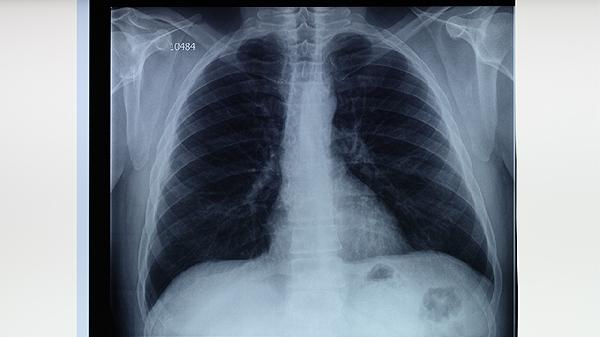

肺結(jié)核盜汗主要表現(xiàn)為夜間睡眠中大量出汗,常伴隨低熱、乏力等癥狀。盜汗可能與結(jié)核分枝桿菌感染引起的免疫反應(yīng)、體溫調(diào)節(jié)異常等因素有關(guān),需結(jié)合痰涂片、胸部影像學(xué)等檢查確診。

肺結(jié)核患者的盜汗通常具有規(guī)律性,多發(fā)生在后半夜或凌晨,出汗量可浸濕衣物或床單,且與環(huán)境溫度無關(guān)。這種盜汗往往持續(xù)數(shù)周以上,普通退熱治療無效。部分患者會同時出現(xiàn)午后潮熱、食欲下降、體重減輕等典型消耗性癥狀。結(jié)核菌產(chǎn)生的毒素作用于下丘腦體溫調(diào)節(jié)中樞,導(dǎo)致植物神經(jīng)功能紊亂是主要機制。病情進展期可能出現(xiàn)咳嗽、咯血等呼吸道癥狀。